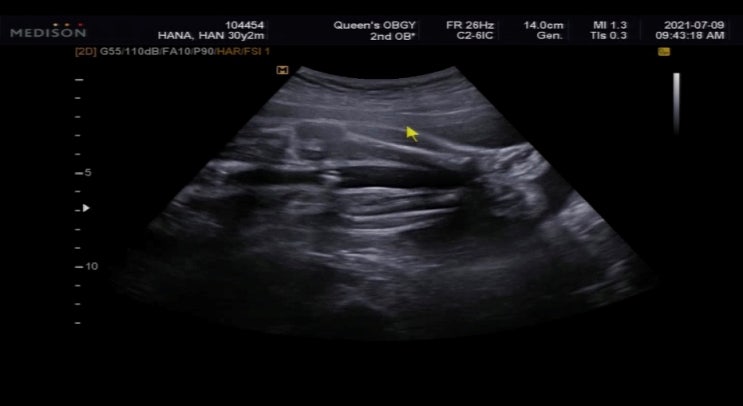

임신 28주차~30주차 기록_ 임신9개월 입체초음파 안 찍어도 될까? 30주 만삭촬영

임신 28주차~30주차 와~ 드디어 9개월차에 입성했어요. 이 아이를 데리고 있던지도 벌써 9개월이라니.. 눈...